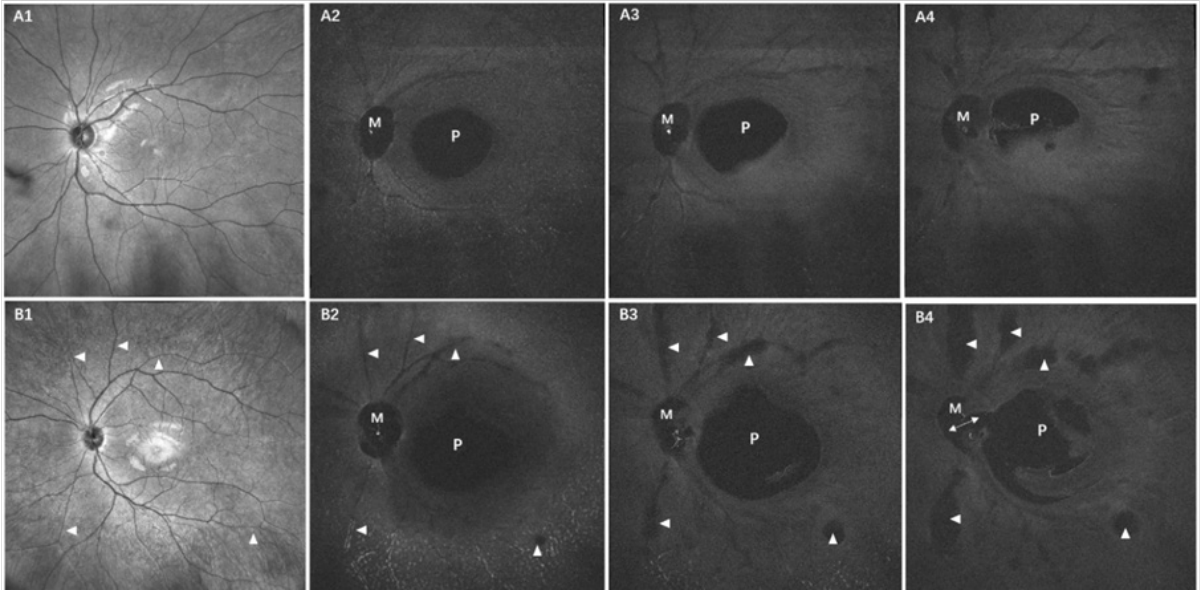

在未成年人中,视网膜前的玻璃体包含4种液化结构,分别是PPVP、AM、PVF和液化池。其中,PPVP被定义为黄斑前的低信号腔隙, AM被定义为视盘前的低信号腔隙,PVF被定义为覆盖视网膜浅层血管的细长低信号腔隙,而液化池是比PVF更宽大的低信号腔隙,其位置与PVF一致,见图1。本研究中,所有眼睛均能检出PPVP、AM和PVF。PPVP位于颞侧血管弓内,直径为(5 318.9±809.6)μ m,且儿童组的(5 325.2±875.0)μ m和少年组的(5 266.1±710.5)μ mPPVP的宽度比较差异无统计学意义(P =0.765)。动态en face投射图(图2)显示其逐渐从椭圆形变成新月形或不规则形,22眼(31.4%)的PPVP和AM在视盘前上方连通。PVF主要位于后部玻璃体并围绕PPVP和AM区域分布,en face图像能够显示PVF沿着视网膜浅表血管走行的连续行径,见图2A2~A4。与PVF位置一样,液化池也沿着视网膜浅层血管分布,且液化池向上逐渐扩大形成更大的液化池,通过动态en face图像评估可以很容易地区分出来,见图2B2~B4。

图 2 动态en face图像评估后玻璃体液化特征

Figure 2 Dynamic en face assessment of posterior vitreous liquefaction